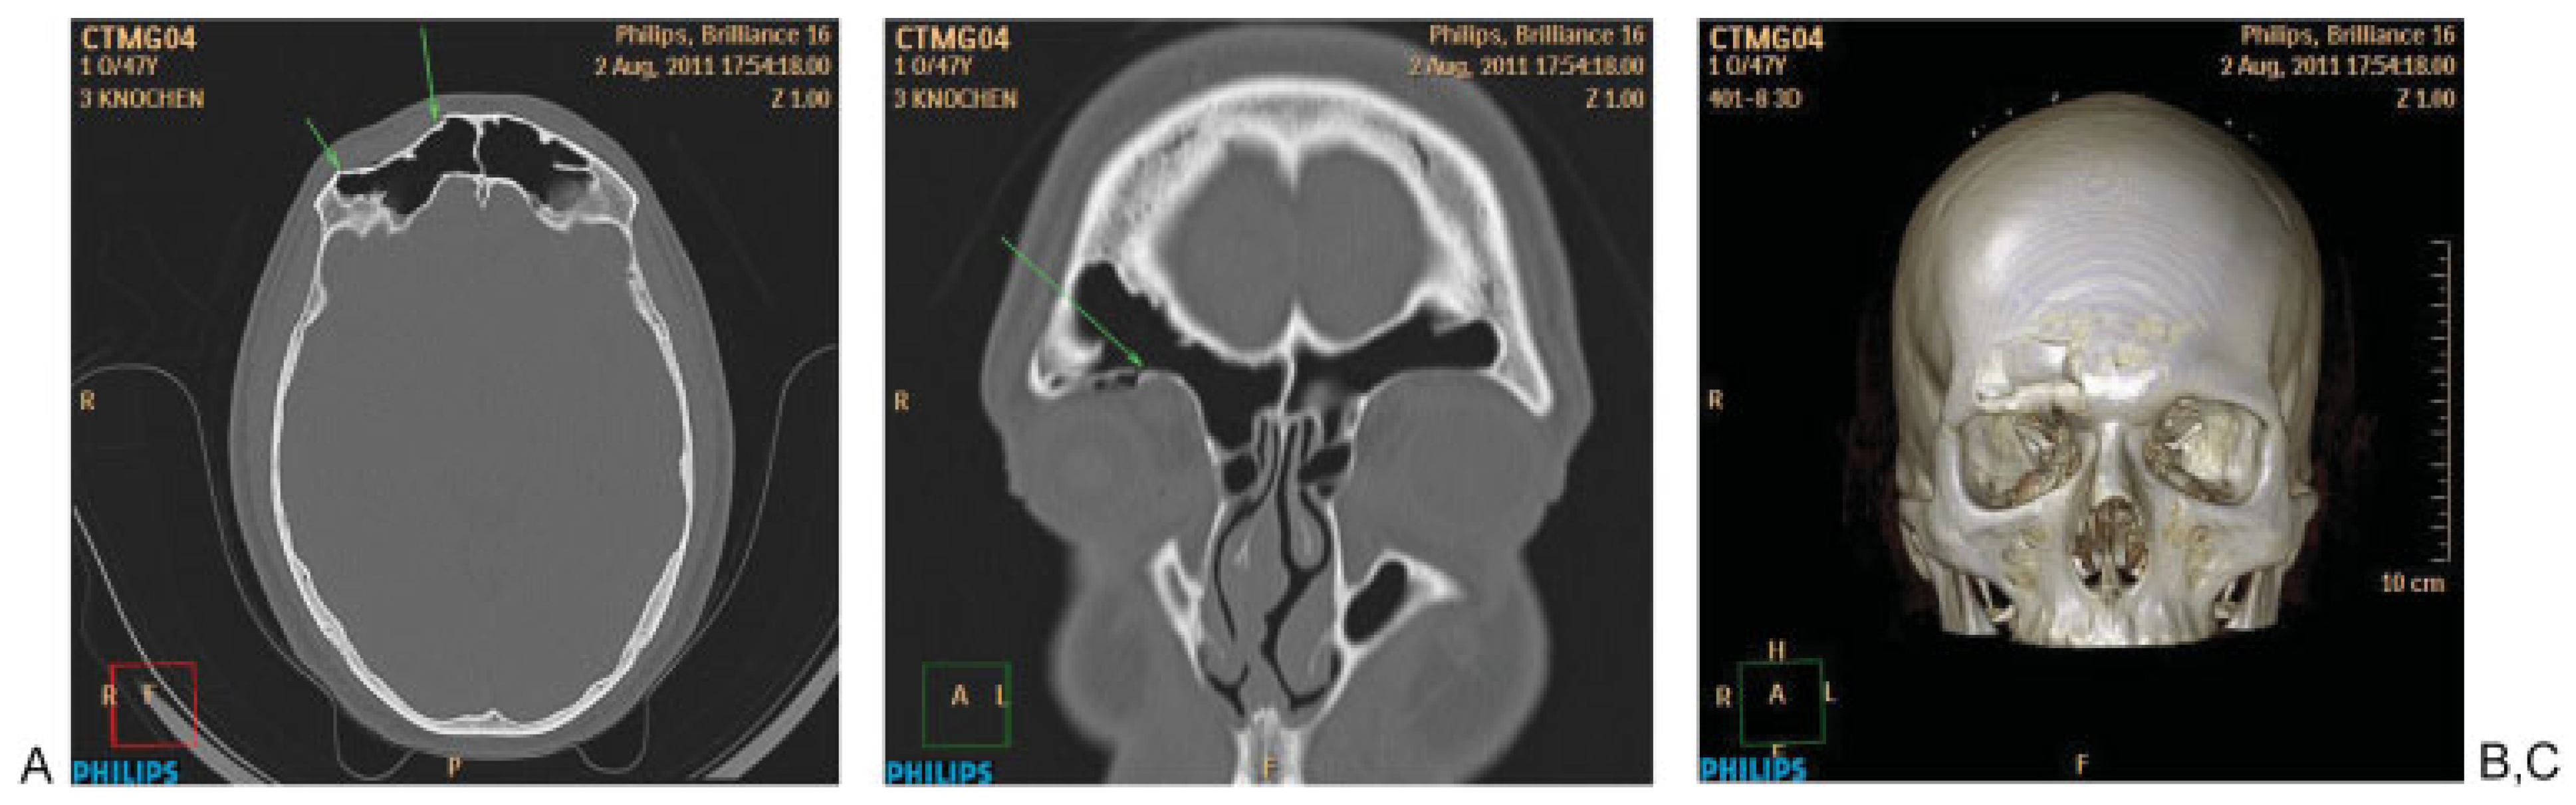

Figure 4. Systematic analysis of skull base/cranial vault fractures. (A) Depressed fracture of the anterior wall of the right frontal bone (F). (B) Twodimensional coronal reconstruction showing involvement of the right orbital roof (anterior Skull Base: ant. SB). (C) Three-dimensional computed tomography reconstruction showing the extent of the fracture.

Systematic evaluation of the skull base and cranial vault in CT (Figure 4) begins with the evaluation of axial slices from caudal to cranial to detect direct fracture signs, especially in the anterior skull base (right or left), central, middle (especially temporal bone fractures) and posterior skull base, in this order. Frontal bone and parietal bone cranial vault structures are then disclosed. 2D reconstructions are especially useful for detection of anterior skull base fractures as well as temporosphenoidal middle skull base fractures. 3D and MIP reconstructions facilitate the definition of the extension of the fractures, especially in cases with some displacement or comminution.